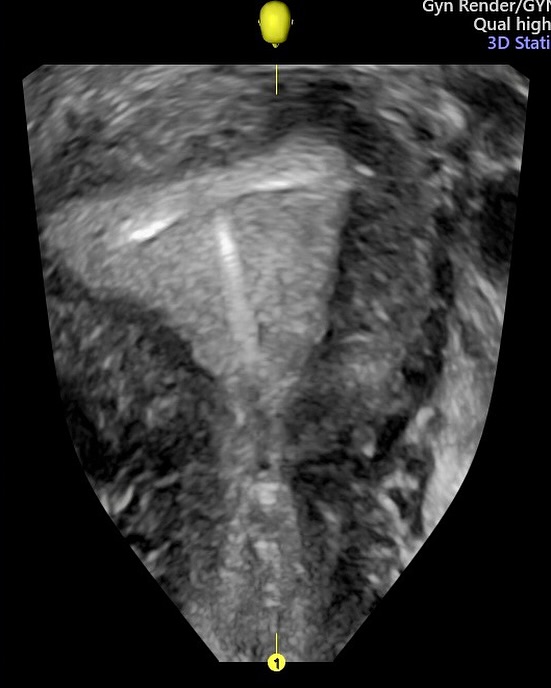

A ultrassonografia em três dimensões (3D) revolucionou a forma como avaliamos o útero e seu interior. Sua capacidade de gerar imagens volumétricas permite uma análise detalhada da cavidade endometrial, com cortes multiplanares que ampliam nossa percepção anatômica e funcional.

- Patologias endometriais, como pólipos, miomas submucosos, sinéquias e malformações uterinas, podem ser visualizadas com mais clareza na ultrassonografia 3D, facilitando o diagnóstico precoce e contribuindo para o planejamento terapêutico mais eficaz.

-  Quando falamos em dispositivo intrauterino (DIU), a avaliação 3D é especialmente útil. A reconstrução volumétrica permite verificar com precisão o posicionamento do DIU, identificando deslocamentos, inserções parciais ou até perfurações, muitas vezes imperceptíveis em exames bidimensionais convencionais.